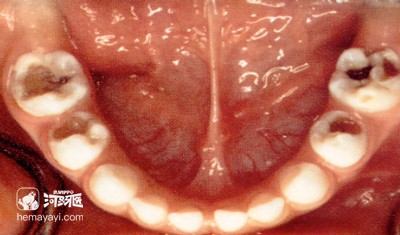

为什么刚萌出的“六龄齿”易患龋?

由于“六龄齿”的形状,它的牙尖最多,咀嚼面凹凸不平,尤其是新长出的恒磨牙上面有很多的窝沟点隙,容易存积食物残渣,而且刷牙也无法清除干净,久而久之被细菌分解产生酸导致牙釉质脱矿,发生龋坏。

刚萌出的“六龄齿”钙化过程尚未完成,坚硬度较低,所以易患龋。

刚萌出的“六龄齿”由于位于乳牙列后方,萌出时间较长,牙齿有龈瓣覆盖造成食物残渣堆积,口腔清洁时难度较大,易于患龋。

由于“六龄齿”萌出最早,“六龄齿”萌出时没有乳牙的脱落,而且形状与第二乳磨牙相似,易被家长误以为是还要替换的乳牙而忽视对它的关注,这些都是“六龄齿”患龋风险增加的原因。